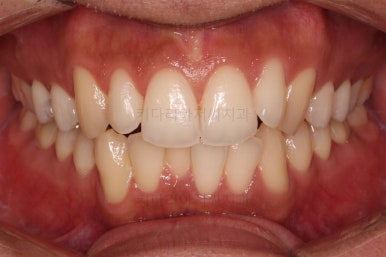

초진 시 입안의 모습입니다.

앞니가 약간 삐뚠 것 말고는 큰 문제는 없어보이네요.